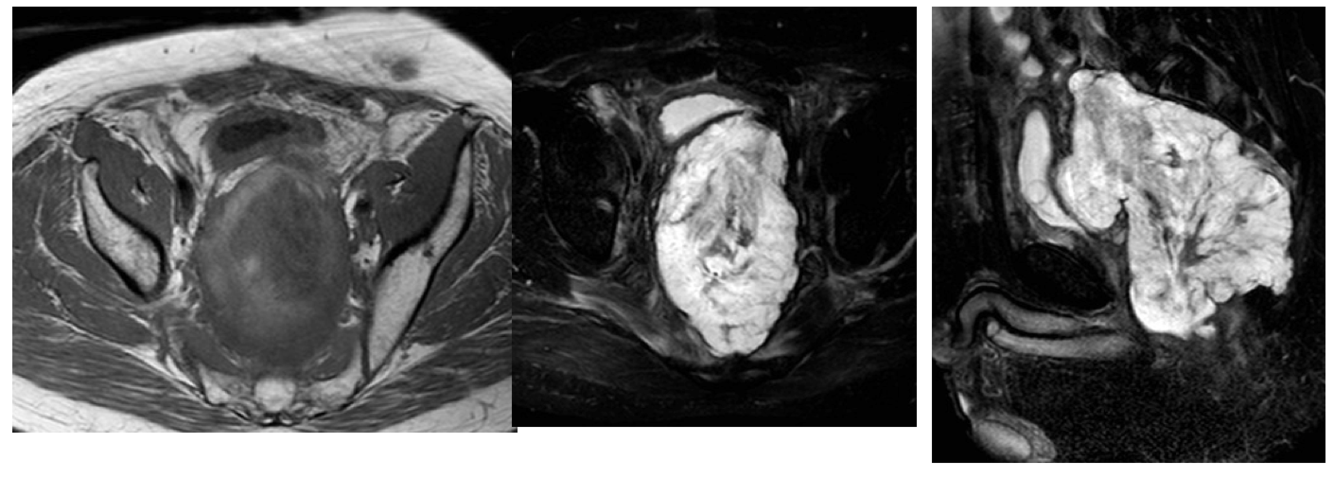

What this be?

Endometrial carcinoma

Cystadenocarcinoma (tissue density changes circled in red help in identification)